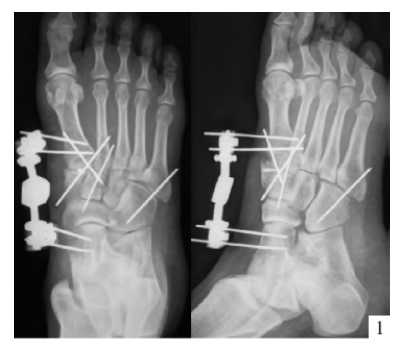

内固定选择1、克氏针:优点是手术简单、时间短、对周围组织损伤小,缺点是固定不坚强、复位丢失等情况时有发生。2、可吸收螺钉:优点是不需行二次手术取出内固定物,缺点是固定强度不及传统螺钉3、小螺钉系统:经典 --- 3.0mm、3.5mm、4.0mm4、空心螺钉:3.0mm、4.0mm、4.3mm 、4.5mm5、微型钢板:跨关节固定,对于严重的跖骨粉碎性骨折的患者,螺钉无法固定时,建议选择微型钢板桥接固定6、骑缝钉

手术切口选择单一切口、双切口

双切口能充分显露所有的跖跗关节;第一切口位于第一、二跖骨之间。该切口利用了两个间隙,一个拇长伸肌腱内侧,一个为拇短伸肌腱外侧。分别可显露第一跖骨、内侧楔骨和第二跖骨、中间楔骨。通过延长皮肤切口,可以直视第三跖骨和外侧楔骨。第二切口位于第四、五跖骨之间,可以显露其与骰骨之间的关节。

根据三柱理论1、首先复位内侧柱并临时固定 2、再复位固定中间柱3、如外侧柱移位可能需双切口

手术从第一跖骨和内侧楔骨开始。首先直视下复位该关节,评价楔骨之间的稳定性,关节囊通常撕裂,但仍然需要掀开以充分显露关节,清除关节内的软组织和软骨碎片内侧柱稳定后,开始处理第二跖骨和中间楔骨。点式复位钳由第二跖骨基底部外侧远端斜向内侧楔骨内侧面的近端夹持,注意避免第二跖骨向下移位,发生复位不良。

若楔间关节仍不稳,可使用楔骨间螺钉;固定内侧两跖骨后,通常第三跖骨已经足够稳定,若仍未复位,可以参考第一跖骨固定方法固定。通过第二切口固定第4、5跖骨。可以使用克氏针固定。

Lisfranc损伤骨折复位标准:1、C形臂透视显示正、侧、斜位均为正常解剖复位2、如复位后第1、2跖骨基底间隙和内、中楔骨间隙<2mm,跖跗骨轴线<15°为近解剖复位,可以接受,超过这个范围的移位则无法接受3、复位好后,沿第一跖骨轴线向内侧楔骨逆行拧入一枚4.0mm皮质骨螺钉。螺钉由关节远侧1.5-2.0cm处进入,平行于足底或略向跖侧。

4、从内侧楔骨向第二跖骨置入一枚螺钉,重建韧带。螺钉自内侧楔骨近端的背侧置入,指向第二跖骨背侧皮质的下方,螺钉应通过4层皮质,确保对第二跖骨的双皮质固定

术后管理石膏固定4~6周;如果固定稳定,术后两周可开始功能锻炼,4~6周部分负重,六周后完全负重;术后6~8周可拔去克氏针,术后3~4月可取出螺钉。有些人主张若无症状出现,可无限期地留置螺钉于体内

单纯克氏针、螺钉固定不适用于粉碎性骨折,特别是合并短缩的骨折,后期易导致畸形愈合。克氏针外固定架联合固定可对内侧柱进行支撑复位;对于内侧柱粉碎骨折患者,微型外固定架有一定的优势。